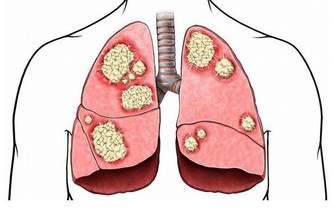

若體內尿酸太多,形成結晶鹽,沉積在腎臟,腎臟長期處在慢性炎症的刺激中,便會功能下降。

腎臟功能一旦受損,排泄廢物(包括尿酸)的能力下降,反過來又會使尿酸水平進一步升高,腎功能進一步受損,形成惡性循環。

不僅如此,沉積的尿酸還可能形成結石,誘發腎絞痛、血尿、腎盂腎炎等。較大的腎結石還可能形成梗阻、腎積水,進一步損傷腎功能。